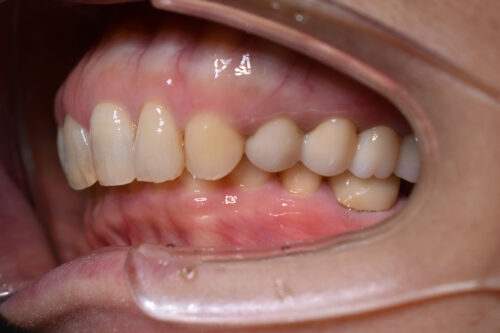

初診時年齢 46歳 女性

歯のでこぼこ(叢生)

左側完全クロスバイトの治療を

左側の小臼歯部から

大臼歯部にかけて

クロスバイトを呈し

過蓋咬合の状態でした。

ワイヤー矯正治療1年2か月後です。

上顎左右臼歯部には

歯科矯正用アンカースクリュー(デュアル・トップオートスクリュー)を用い

下あごを オートローテーションさせ

また 上下の歯列全体を

後方へ移動させることで

また 下あごの反時計回り

オートローテーションを 行うことで

歯を抜かなくても

口元の改善も行えます。

本症例では

左側の完全クロスバイトにより

顎が変形しておりましたが、

矯正治療単独の矯正治療でも

かみ合わせを 正しくすることで

臨床治療においては

お顔立ちの曲がりも 良くなることが多いです。